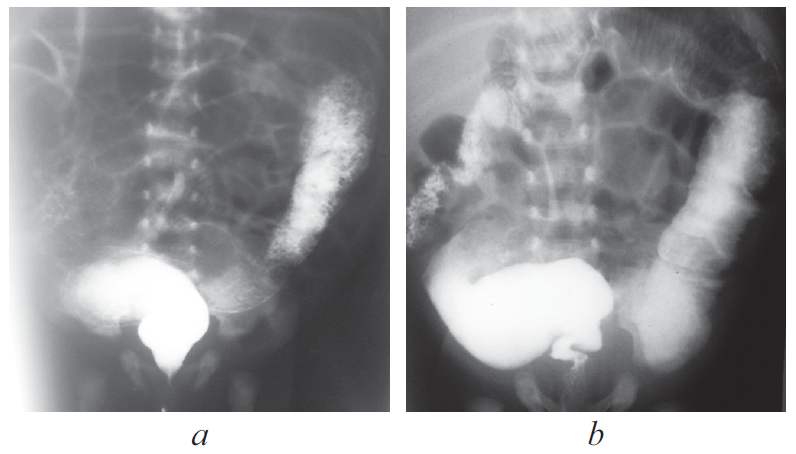

Hirschsprung’s disease usually manifests from the first days of life and is diagnosed in the newborn period. In some patients Hirschsprung’s disease can’t be diagnosed in the newborn period because of different forms of disease and clinical features. From 2008 to 2019 75 patients with Hirschsprung’s disease were operated in the City Children’s Hospital No. 1. 21 patients had delayed diagnosis. 11 newborns didn’t have very clear clinical symptoms, intestinal obstruction disappeared after decompression. 2 patients with associated chromosomal disorders were diagnosed with Hirschsprung’s disease later because of. In some of older patients disease manifested with severe constipations. Also, we presented some clinical cases of major diagnostic errors in patients with Hirschsprung’s disease. Conclusion. Diagnostic errors in patients with Hirschsprung’s disease are associated with the lack of alertness of neonatologists and inadequate interpretation of clinical manifestations and X-ray study. For many years these children can be treated by different specialists before having surgical consult.